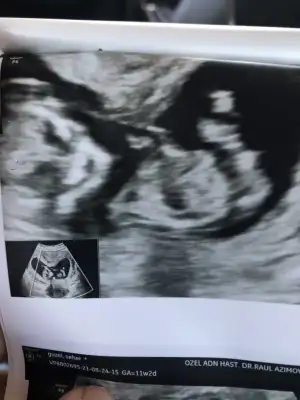

Merhaba canım doktor kordon mu erkek mi karar veremedi 2 hafta sonra bi daha gel dedi başta erkek diyecektim sonra kordon olduğunu anladım dedi kesin bişey diyemiyorum dedi sen bi bakabilir misin 🥺🙏🏻🙏🏻♥️♥️♥️ Ikra meyra Ikra meyra Ikra meyra Ikra meyra

• 20ABBA81-603F-4423-BCBD-0A1C998B04DA.webp

20ABBA81-603F-4423-BCBD-0A1C998B04DA.webp

21,6 KB · Görüntüleme: 100